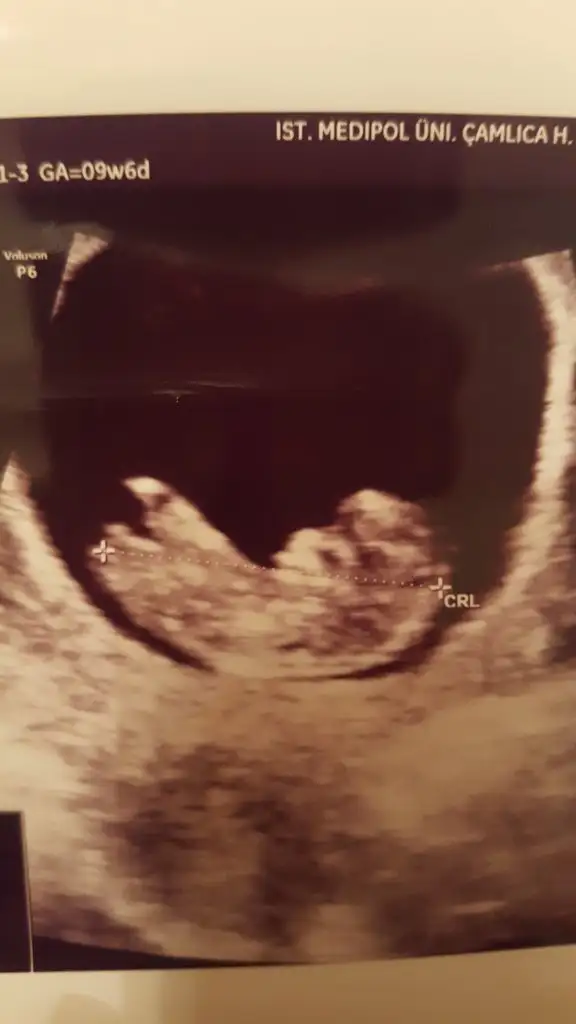

Kızlar sizce bebişimin cinsiyeti nedir?

Bir de bunlara bakın isterseniz